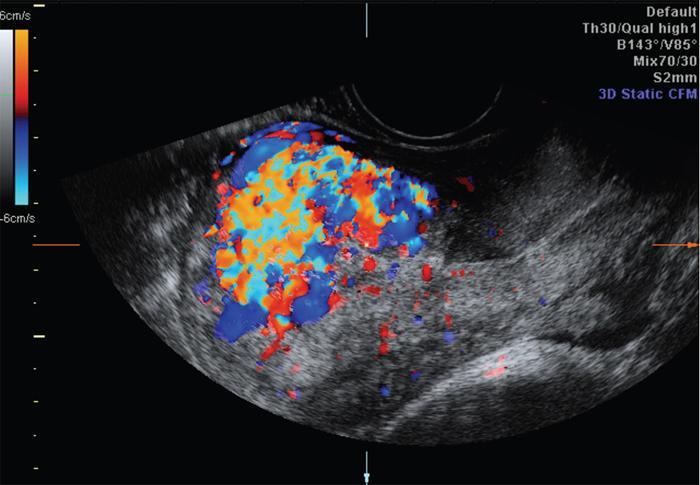

John De Lindsay, Sumathy, Vasumathy, Usha nandhini Ganeshan, N. Sundari ENDOMETRITIS Endometritis is defined as the inflammation of the uterine endometrial layer. Endometritis is frequently observed in the pregnant and postpartum population. Pelvic inflammatory disease (PID) and invasive gynaecological procedures are the most common causes of acute endometritis in nonobstetric population. Endometritis is the most complex asymptomatic and often presents with subclinical form of PID. Ultrasound may reveal minimal particulate endometrial fluid with mildly thickened endometrium showing increased vascularity. Computed tomography (CT) findings include a diffusely bulky uterus due by inflammation, mild fluid distension of endometrial cavity and striking endometrial enhancement in comparison to the adjacent myometrium due to mucosal hyperaemia. ‘Indistinct uterine border’ sign is observed in patients with endometritis, which is defined as the loss of distinction between the uterus and the adnexa. Since it is also observed in the cases of endometriosis or malignancy, it is a nonspecific sign. The age of the patient, clinical presentation, and the biopsy of endometrium helps in differentiating endometritis from other pathologies. UTERINE ARTERIOVENOUS MALFORMATION Uterine arteriovenous malformation (UAVM) is an abnormal connection between the arteries and the veins of the uterine myometrium without an intervening capillary bed. They were first reported by Dubreil and Loubat in 1926. They can be congenital or acquired. Even though UAVMs have varied presentation, uterine bleeding is the most common one. They often follow a pregnancy event. Episodic or occasionally torrential vaginal bleeding can occur. Congestive heart failure secondary to vascular steal can be a rare presentation due to a large UAVM. UAVM is most commonly an acquired condition. Pregnancy has a significant role in their pathogenesis. It is most commonly observed in reproductive age group. UAVMs are frequently observed in the postpartum period, few months after spontaneous miscarriage, surgical evacuation of uterus for miscarriage or medical termination of pregnancy. Infection, inflammation, retained products of conception (RPOC), gestational trophoblastic disease (GTD), gynaecologic malignancies, pelvic trauma and exposure to diethylstilboestrol can also lead to UAVMs. Few cases are also reported in young adolescent and postmenopausal females. UAVMs rarely are congenital and may be also associated with AVMs in other locations. Congenital AVMs Congenital AVMs have a central nidus with multiple feeding arteries and draining veins. In this condition, there is extension of the lesion beyond that uterus and multiple pelvic vessels other than uterine vessels draining into them. That cause of congenital AVMs are thought to be due to failure of embryological differentiation. With the progression of pregnancy, these vessels have the propensity to invade surrounding structures. Iatrogenic Acquired AVMs When the venous sinuses are incorporated into the scars of myometrium after the necrosis of chorionic villi, acquired malformations may arise. In contradiction to congenital AVMs, acquired AVMs multiple fistulous communication between the intramural arteries and the venous plexus. These AVMs may have either dual blood supply or a single supply from the uterine arteries and presents without nidus. Vaginal bleeding caused by pregnancy-related causes must be differentiated from UAVMs. Surgery/evacuation is the appropriate management for the former and the same is contraindicated in the UAVMs and hence an accurate definitive diagnosis is important. Grey-scale ultrasound findings are nonspecific and they are subtle heterogeneity of myometrium with multiple tubular or ‘spongy’ anechoic or hypoechoic areas. In spite of varied presentations such as an intramural uterine, endometrial or cervical mass-like lesions or prominent parametrial vessels, it has minimal mass effect. On colour Doppler, within the myometrium, a region of increased vascularity and most commonly with aliasing is seen. A group of vessels traversing the myometrium running perpendicular to and into the endometrium, from the arcuate vessels, can be seen. It is not specific, as they are also observed in RPOC, GTD, placental polyp and vascular endometrial neoplasm. In pulsed Doppler, multidirectional turbulent flow with intense vascularity can be seen with high peak velocity (mean peak systolic velocity [PSV] = 136 cm/s) and low resistance (mean resistance index = 0.3) flow. The arteries have low pulsatility while the draining veins are pulsatile and show high velocity flow. Magnetic resonance imaging (MRI) offers noninvasive confirmation of the diagnosis of UAVM. T1-weighted and T2-weighted images show multiple serpentine signal voids along the uterine wall, endometrial cavity and parametrium. Contrast-enhanced MR angiography shows intensely enhancing complex serpentine abnormal vessels with early venous return. Catheter angiography can be reserved only for women who require embolization of the AVM. The consent for both diagnostic angiography and therapeutic embolization should be obtained simultaneously to avoid repeat therapeutic procedures. Management of UAVM depends on: UAVM can be treated with medical therapy with hormones, uterine artery embolization or with definitive hysterectomy. Once the diagnosis of a UAVM is confirmed, the treatment option depends on the clinical condition of the patient. The size of the AVM bears no correlation to the need for embolization. Timmerman et al. found that AVMs having PSV of at or above 0.83 m/s, most often requires embolization. Also, the vascular malformation with PSV value below 0.39 m/s does not require embolization. Placental bed subinvolution, enhanced myometrial vascularity (EMV), molar pregnancy or RPOC are the other causes of uterine mass vascular malformations which usually has a mean PSV of 0.52 m/s and does not require embolization. Transcatheter targeted uterine artery embolization is indicated in selected cases, if bleeding persists to a degree that blood transfusions are required to maintain haemodynamic stability or multiple repeated acute hospitalizations. This is preferred over surgical management owing to its immediate minimally invasive and fertility sparing benefits. Gelfoam had been suggested earlier as the material of choice for embolization. Various other embolic materials like polyvinyl alcohol, Histoacryl glue, stainless steel coils, detachable balloons, and haemostatic gelatin are also used nowadays. Normal intrauterine pregnancies after embolization have been reported, proving that an adequate collateral blood supply can develop to support a full-term pregnancy. Gestational Trophoblastic Disease RPOC: Presence of endometrial pathology rather than myometrial origin. FIBROIDS Leiomyomas, also known as fibroids or myomas, are the most common gynaecologic neoplasms, occurring in 20%–30% of women of reproductive age. Symptomatic uterine fibroid accounts for about 30% of hysterectomies performed for women older than 18 years of age and 41% of hysterectomies performed for women from 44 to 64 years of age. Leiomyomas are the benign neoplasms made up of whorled fascicles of smooth muscle and fibrous connective attached to the uterine muscular wall. Even in the absence of true capsule, leiomyomas are well circumscribed and contains a pseudocapsule. Its size is variable, ranging from tiny microscopic to large tumours filling the abdomen. Most commonly, the uterine leiomyomas are seen in the myometrium of uterine corpus. However, it is also seen in the cervix (<5% of cases). On the basis of the location, uterine fibroids are classified as submucosal, intramural or subserosal. This classification is of clinical significance because the symptoms and treatment vary among these subtypes of leiomyomas. Submucosal myomas are further subclassified as 0, I and II depending on the percentage within the endometrial cavity. The first two categories can be removed hysteroscopically (Table 11.15.3.1). Pedunculated leiomyomas are attached to the uterus by a stalk and may be either intracavitary or exophytic (narrower than 50% of diameter of myoma). Rarely, a submucosal fibroid may grow pedunculated and extends into the cervical canal or vaginal canal and its prevalence is about 2.5%. Pedunculated subserosal leiomyomas may undergo torsion, resulting in infarction accompanied by pain. Lateral growth into broad ligament leads to intraligamentous leiomyoma (Table 11.15.3.1). Rarely, a pedunculated leiomyoma may become detached from the uterus (parasitic leiomyoma). Depending on the location, size and number of uterine fibroids, it has varied presentation. Symptoms caused by leiomyomas are classified into three different categories such as abnormal uterine bleeding, pelvic pressure and pain and reproductive dysfunction. Submucosal leiomyomas and intramural leiomyomas are often associated with menorrhagia (Table 11.15.3.1). Because of leiomyoma, uterus may be irregularly shaped and causes symptoms based on their locations. Anterior leiomyomas cause urinary symptoms, whereas the posterior leiomyomas cause constipation. Ureter may be compressed by broad ligament leiomyomas and presents as hydroureter or hydronephrosis. In case of degeneration or torsion of a pedunculated leiomyoma, acute pain may be the presentation. Leiomyomas are an infrequent primary cause of infertility. Malpresentation, pregnancy failures and dystocia are reported. Ultrasound is the first-line imaging modality because it is a cost-effective portable real-time examination that provides good anatomic detail. Leiomyomas appear as a well-defined round or oval hypoechoic solid mass. It is mostly associated with posterior shadowing possibly due to calcifications or interface of the margins of the leiomyoma with the normal myometrium. Degeneration or lipoleiomyoma can be suggested when there is internal echo-poor or hyperechoic foci, respectively. The presence of hypervascularity in a large solitary uterine mass can identify suspicious masses, such as a leiomyosarcoma (LMS). Another study found that there is an increased detection rate of uterine sarcomas while using a cut-off value of 41 cm/s. In the assessment of a uterus enlarged with multiple leiomyomas, ultrasound has FOV limitations. Likewise, it has limited role in the assessment of retroverted uteri, pedunculated subserosal myomas and concomitant adnexal processes. Little has been reported regarding sonographic changes after MR HIFU and uterine fibroid embolization (UFE). Differential diagnosis has been discussed in Table 11.15.3.2. Hyperechoic unlike a myomatous polyp which appears hypoechoic Heterogeneous endometrium with little mass effect Enlarged uterus and a deformed contour are the most common computed tomography (CT) findings. Even though CT is the primary modality for the staging of cancers, it has limitation of reduced contrast resolution for the assessment of focal myometrial masses, and associated with risk of ionizing radiation. Also, in delineating the zonal anatomy for accurate localization of leiomyomas and LMSs, CT is inferior to magnetic resonance imaging (MRI). More often dense or amorphous calcification is seen. Almost exclusively, on plain radiography or CT, these patterns of calcification favours the diagnosis of leiomyoma. Ring-like calcification at the margins of a leiomyoma is a rarely observed pattern, which represents the thrombosed veins. Positron emission tomography (PET)/CT is an ideal modality for the confirmation of malignancy and also helps in detection of metastasis and recurrence. In a small study of patients with histopathologically confirmed uterine sarcoma found that on comparing with the findings of MRI and ultrasound with power Doppler imaging, the results of fluorodeoxyglucose (FDG) PET examinations were 100% positive. However, it has limitations such as increased false-positive rate and reduced widespread availability. MRI appearance of leiomyomas: MRI is considered as the most accurate imaging technique for the detection and localization of leiomyomas. In determining the presence and location of leiomyomas in infertile women before myomectomy, MRI has been shown to be more accurate and sensitive than US or hysterosalpingography. Nondegenerated uterine leiomyomas usually has a typical MRI appearance of (Table 11.15.3.4) well-circumscribed masses with homogeneously decreased T2-weighted signal intensity. TABLE 11.15.3.3 Note: SI, signal intensity; ADC, apparent diffusion coefficient. Compared with that of normal smooth muscle myometrium. Degenerated leiomyomas have varied imaging appearances on T1-weighted, T2-weighted and contrast-enhanced images as described in Tables 11.15.3.4 and 11.15.3.5. Hyaline Oedema *Common *50% cases *Usually peripheral Cystic Myxoid Carneous, red, or UAE associated Calcific Leiomyoma variants (Tables 11.15.3.4 and 11.15.3.6): There are several, such as mitotically active, cellular and atypical leiomyomas, as well as smooth muscle tumours of uncertain malignant potential (STUMP). On histopathological examination, the nondegenerated fibroids are made up of goals of uniform smooth muscles with varied amounts of collagen. Cellular leiomyomas, which are composed of compact smooth muscles cells only with no collagen, will demonstrate increased T2-weighted signal intensity and homogeneous enhancement. There is a greater risk of recurrence in case of atypical leiomyomas and uterine STUMP. The patients who had undergone myomectomy and were found to have atypical leiomyoma, must be under surveillance with an annual pelvic ultrasound or MRI. Since the recurrences may presents as pelvic or abdominal masses or as pulmonary metastases, for all the patients with STUMP lesions, routine physical examinations, including pelvic examinations and the baseline CT of the chest, abdomen and the pelvis are recommended for every 6 months for 5 years and then annually thereafter. In addition, prompt re-exploration and staging is recommended for patients with STUMP who have undergone a morcellation myomectomy. An aggressive imaging surveillance is considered, when the disease is present. Atypical leiomyomas and STUMPs routinely express progestin receptors; however, because of the low recurrence rates, there is no role for adjuvant hormonal therapy. Atypical uterine masses can be treated surgically with hysterectomy or myomectomy. Histologic subtype Cellular leiomyoma Round or oval Single large lesion with absence of coexistent adenomyosis Responds to GnRH analogues Cured with surgery No need for follow-up Lipoleiomyoma Well defined: round or oval STUMP Round or oval Intense surveillance Note: SI, signal intensity; ADC, apparent diffusion coefficient; UAE, uterine artery embolization; STUMP, smooth muscle tumours of uncertain malignant potential. Being a benign neoplasm, fibroids usually have a pushing border and rounded edges. But, specific types of fibroids represent growth pattern variations, such as intravenous leiomyomatosis, metastasizing leiomyoma, diffuse leiomyomatosis and peritoneal disseminated leiomyomatosis. Retroperitoneal growth and parasitic growth are the other atypical growth patterns. Even cervical and vaginal leiomyomas may show growth pattern. It is important to note that adenomyosis and focal myometrial contraction can coexist and distinction is important at preprocedure imaging (Table 11.15.3.7).